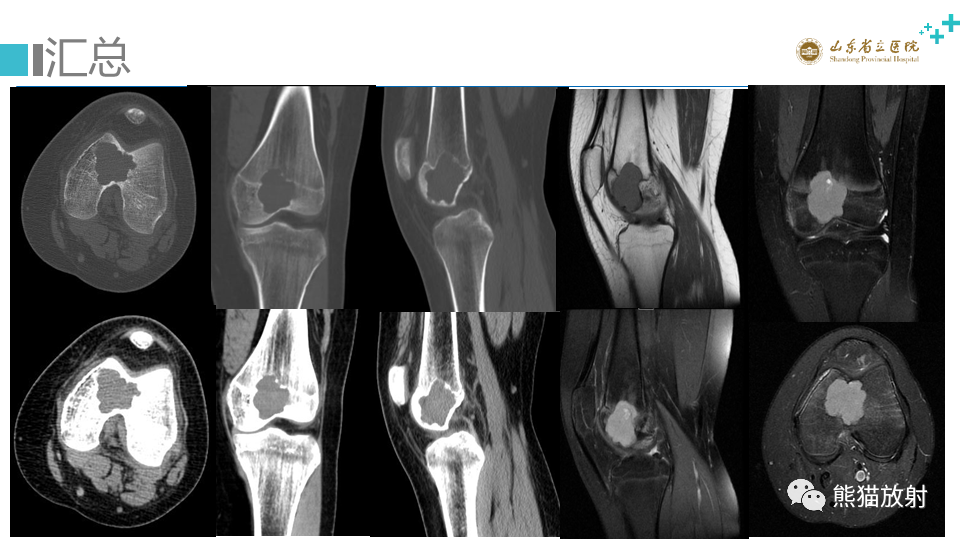

【病例】股骨远端动脉瘤样骨囊肿ABC VS 软骨母细胞瘤-7

【病例】股骨远端动脉瘤样骨囊肿ABC VS 软骨母细胞瘤-8